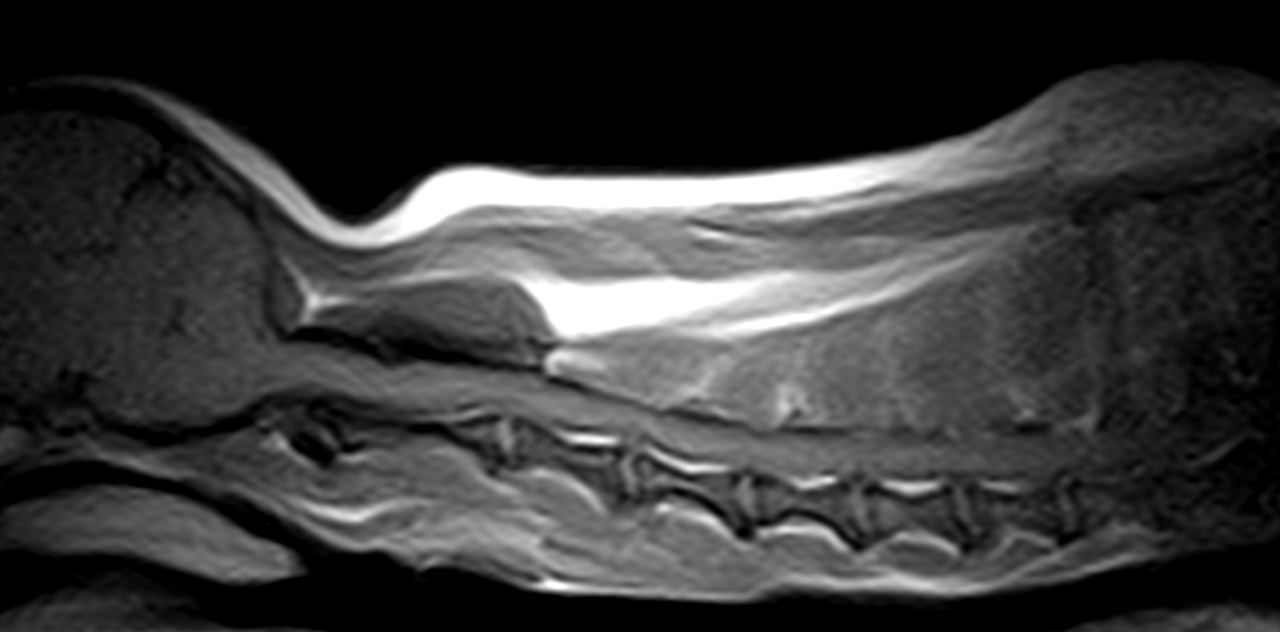

Ventral Slot チワワちゃんの頸部椎間板ヘルニアC3~C4 Ventral Slotで脊髄減圧術。しばらくは安静が必要です。 症例カテゴリー 放射線治療整形外科軟部組織外科脳神経外科内科腫瘍外科救急・集中治療リハビリテーション科腫瘍内科内視鏡科脳神経科呼吸器外科中医・漢方猫の腎移植循環器科